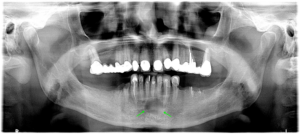

Darstellung eines Röntgenbilds mit einer Kieferzyste mit umliegendem Knochenabbau vor chirurgischer Behandlung